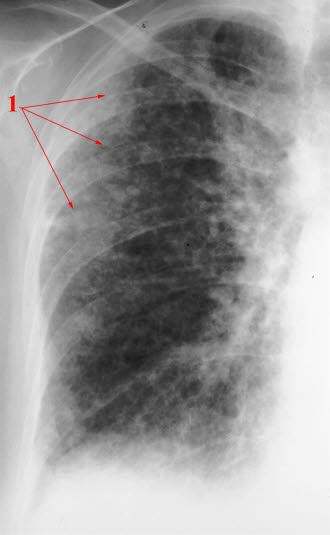

Lungefibrose (HRCT)Lungefibrose er en tilstand med betennelse og økt mengde bindevev (arrvev) i lungene. Arrdannelse er kroppens måte å reparere vevsskade på, ikke bare i lungene, men i hele kroppen. Det er sammenlignbart med et arr i huden etter et skrubbsår. Ved lungefibrose er det unormal arrdannelse i lungeblærene. Når det dannes arr isteden for normalt lungevev, blir gassutvekslingen mellom lunge og blod dårligere enn normalt. Lungene blir stivere og mindre bevegelige, og det arealet som kan brukes til gassutveksling, minker. Har man lett grad av lungefibrose, er det ikke sikkert man merker det på pusten, men jo mer fibrose som dannes, jo tyngre blir det å puste.

Legen foretar en fysisk undersøkelse og tar blodprøver for å komme nærmere diagnosen. Lungefunksjonsprøver (spirometri) kan si mye om hvilken type lungesykdom det dreier seg om. Lungefibrose vil nesten alltid vises på et røntgen-/CT-bilde av lungene. Dersom man fortsatt er i tvil etter røntgen/CT, kan man ta en vevsprøve fra lungene og undersøke denne i et mikroskop.